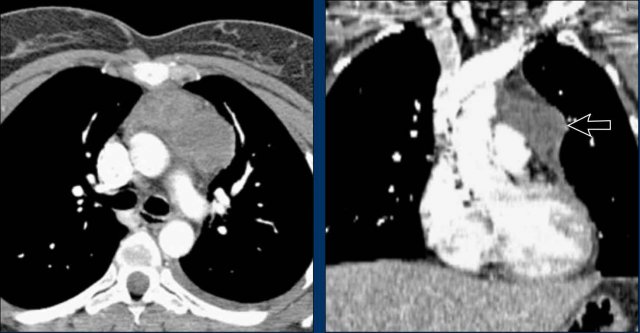

Case Example 1: Pericardial Effusion Mimicking Cardiomegaly

• On the chest radiograph, the patient appears to have a dilated heart.

• However, CT imaging clearly demonstrates that the apparent enlargement is due to significant pericardial fluid accumulation, not true myocardial chamber enlargement.

Postoperative Pericardial Hemorrhage

In patients with recent cardiac surgery, a sudden change in heart size on chest X-ray should raise suspicion for pericardial bleeding, which may be life-threatening.

Case Example 2:

• A postoperative patient showed a change in the cardiac silhouette.

• Echocardiography detected only a minimal pericardial effusion.

Case Example 2 - CT imaging

• CT imaging revealed a large posterior pericardial effusion compressing the left ventricle (blue arrow: effusion; red arrow: compressed, contrast-filled left ventricle).

• Surgical exploration confirmed a large posterior pericardial hematoma.

Note

: Minimal anterior fluid on ultrasound may underestimate the true volume if the effusion is loculated posteriorly, highlighting the value of CT in postoperative cases.